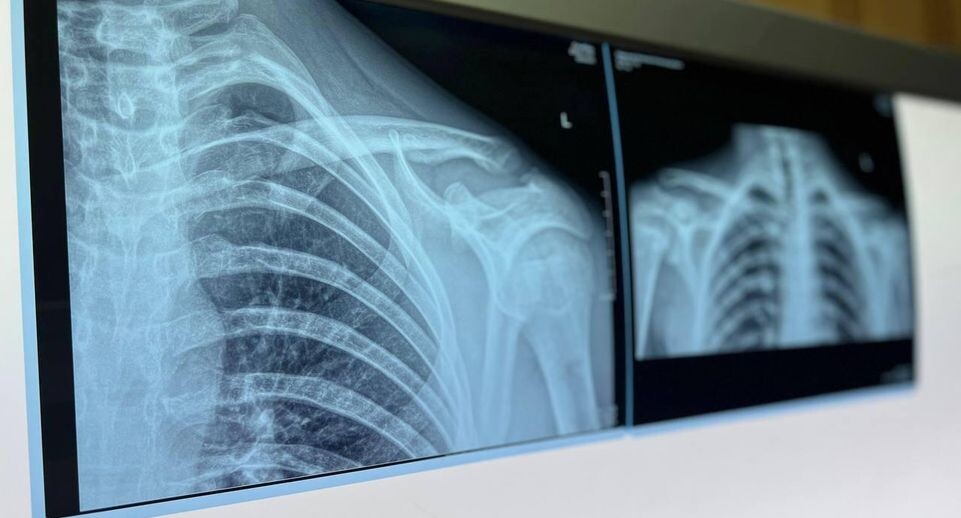

«Они учатся ездить на велосипеде, качаются на качелях и рассекают на роликовых коньках. Все это приводит к нежелательным падениям, в результате которых дети чаще всего получают переломы предплечья, плечевой кости и костей голени», — пояснил главный врач Московской областной детской клинической травматолого-ортопедической больницы Александр Григорьев.

В случае получения травмы врач советует сначала оценить ее тяжесть. При легких повреждениях можно обратиться в ближайший травмпункт, при серьезных — немедленно вызывать скорую помощь.